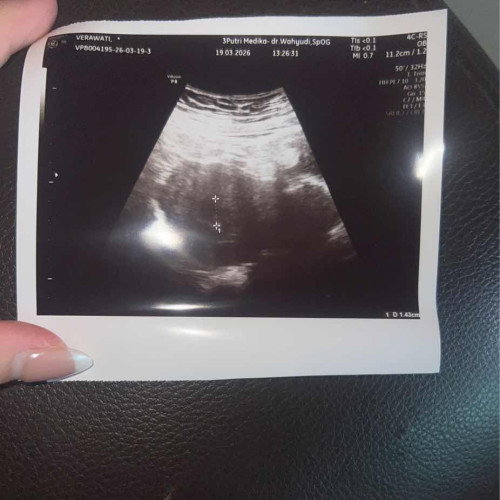

Hasil foto usg

Tolong bantu jelasakan hasil usg tersebut

masih kantung itu, udh ada crl nya. 2-3mggu kedepan coba usg lg, sekalian tnya spog nya. itu yg di print suruh jls in. soalnya aku tiap usg gt, aku minta penjelasan hasil print usg, krn meskipun waktu usg sdh di jlskam, trs hasil di print, aku masih blm paham makna tulisannya apa? jd aku pgn tau, arti dri tulisan ini apa? alhamdulillah nya ktmu dokter yg mau jls in, dg detail dan rinci. jd kedepannya g prlu brtnya" lg

Đọc thêmitu kaya nya masih kantong ya Bun blm ada janin nya, coba bulan depan periksa lg Bun, karna bunda2 disini gk bisa mengartikan dengan pasti arti foto itu. maaf ya Bun, waktu USG apa tidak di jelaskan sama dokternya??? apa bunda tidak bertanya??? kalau dokter tidak menjelaskan dan bunda ada pertanyaan mending di tanyakan langsung, kalau dokternya di rasa kurang cocok menurut bunda mending cari dokter lain.

itu msih kantung bun, aku jga sma kek kmu udh di jelasin oleh dokter spog nya tpi pas drmh lupa akhirnya nanya di chtgpt minta jelasin kode usg itu hhii

itu masih kantung kayanya tunggu beberapa bulan lagi untuk menjadi janin... huhuhu itu cma prediksi aaja aku bukan dokter